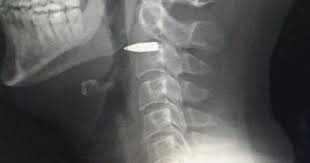

| Subject | 총상 환자에서 꺼낸 총알 |

..그 총알 비브라늄인가? 0